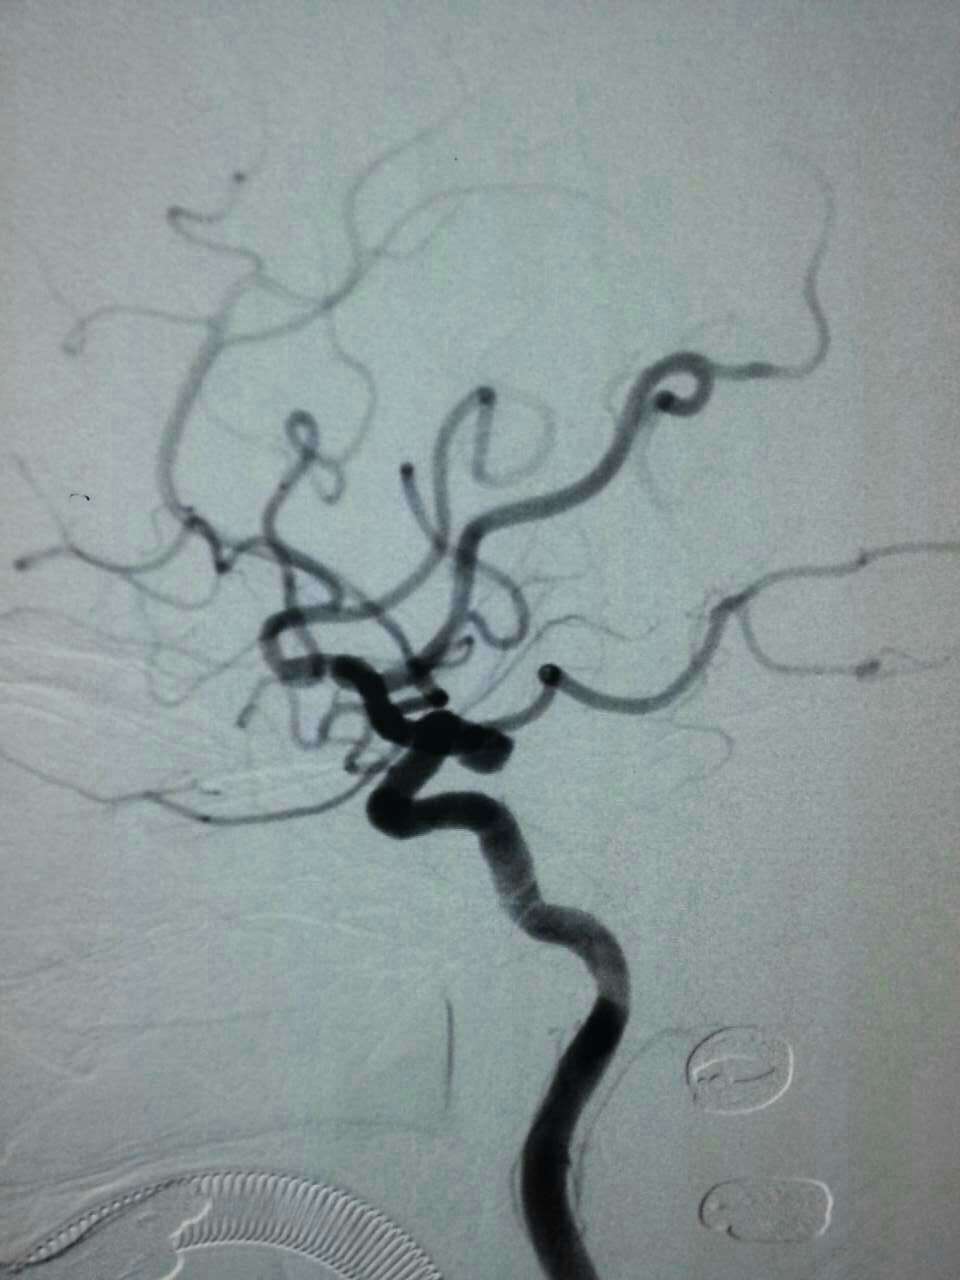

神经外科每年应用介入栓塞技术抢救颅内动脉瘤破裂患者上百例。昨天晚上,陈金龙副主任医师、何雪阳等技术团队又成功抢救来自同安莲花一位80岁叶女士,大量蛛网膜下腔出血,手术顺利,现患者已清醒,可自行进食。